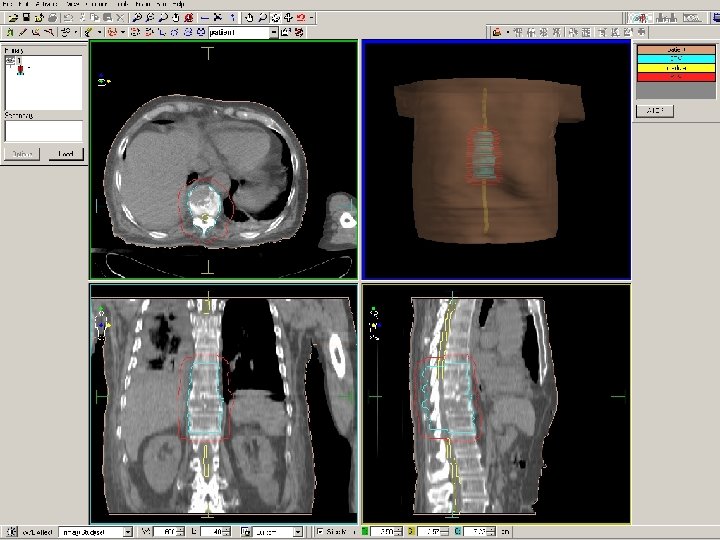

TECNICA DE RADIOTERAPIA n Volumen de tratamiento incluye la región afecta mas una vértebra superior e inferior. n Se realiza TC y planificación 3 D, por lo que la técnica de irradiación se individualiza para conseguir una dosis lo mas homogénea posible. n Esquemas de tratamiento ¡ Corto: 1 x 8 Gy; 5 x 4 Gy ¡ Largo: 10 x 3 Gy; 15 x 2, 5 c. Gy; 20 x 2 Gy n La utilización de uno u otro esquema depende de la expectativa de vida del paciente y de su estado neurológico.